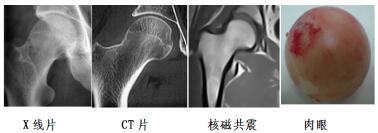

坏死股骨头

股骨头(连接大腿和臀部的一个关节)坏死全称股骨头缺血性坏死,是一种由股骨(即大腿骨)血供中断或受损,引起骨细胞和骨髓成份死亡及随后的修复,继而导致骨头结构改变,股骨头塌陷,从而引发关节功能发生障碍的疾病。